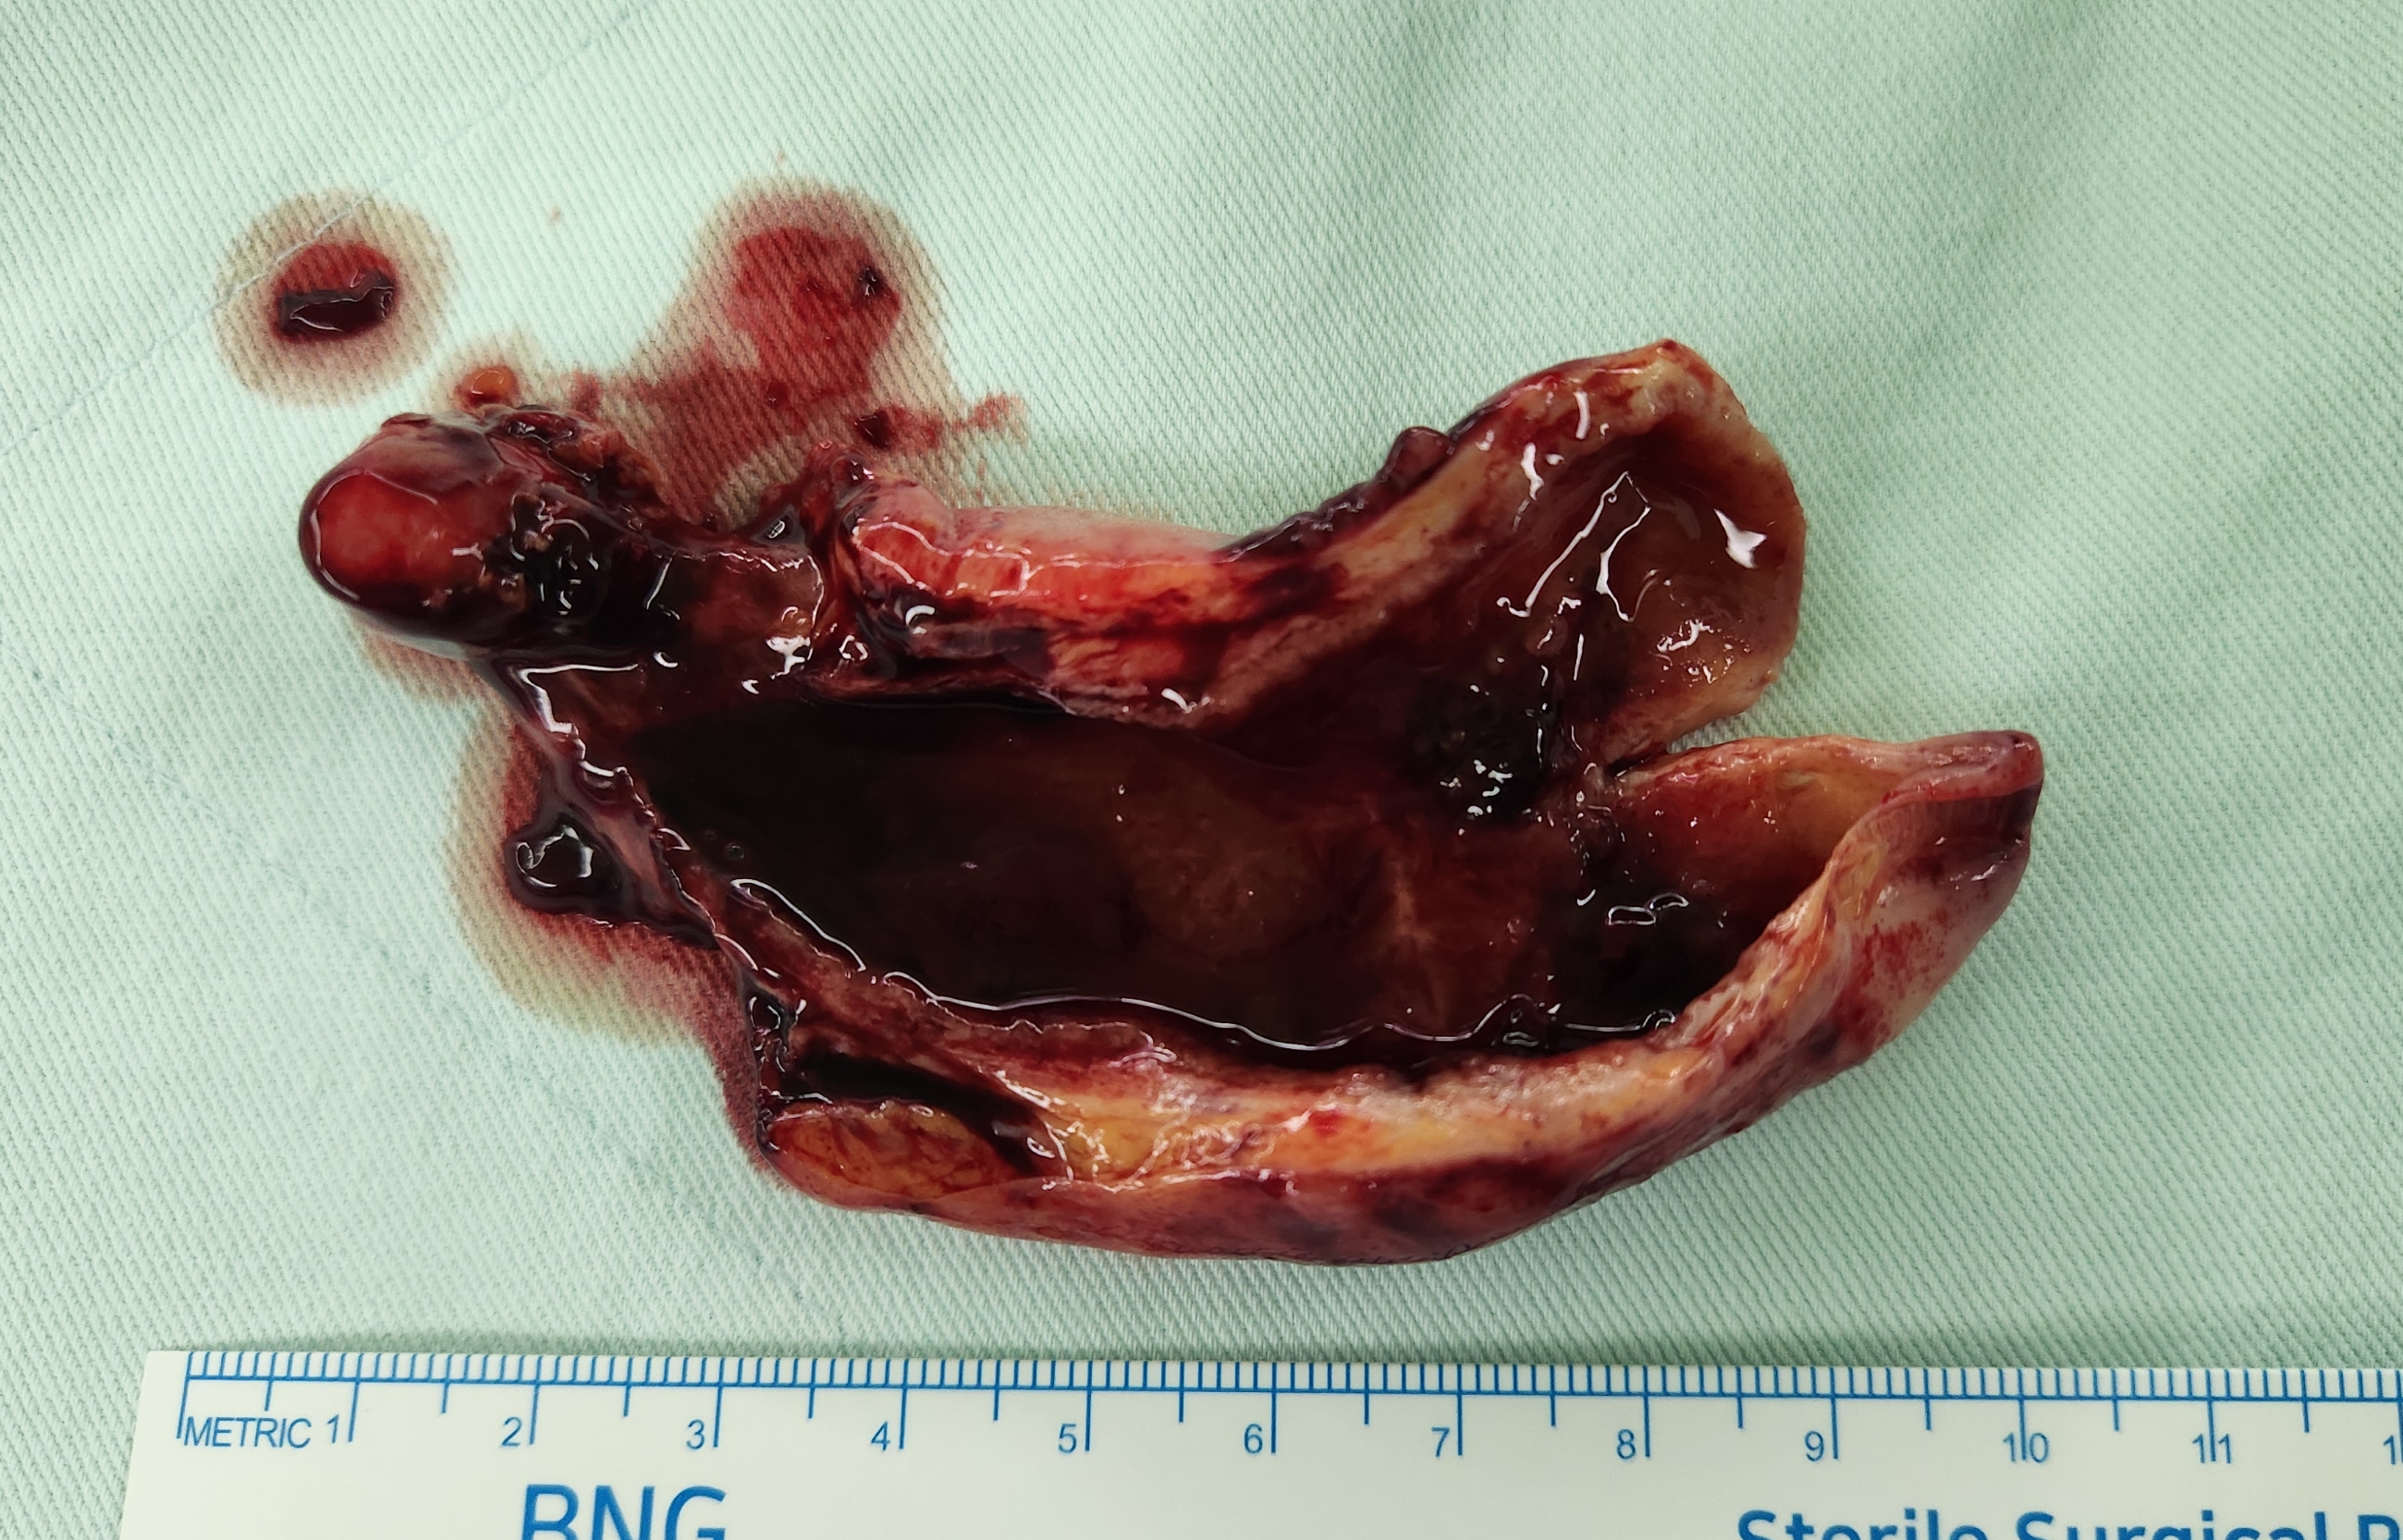

복통으로 8월25일 응급실 내원하여 총담관 결석으로 진단후,

2일전 ERCP시행하여 총담관결석 제거후,

오늘 오전에 담낭염으로 담낭절제 위해 제게 의뢰가 되었고,

방금 복강경 담낭절제술을 시행했습니다.

수술은 30분 걸렸습니다.